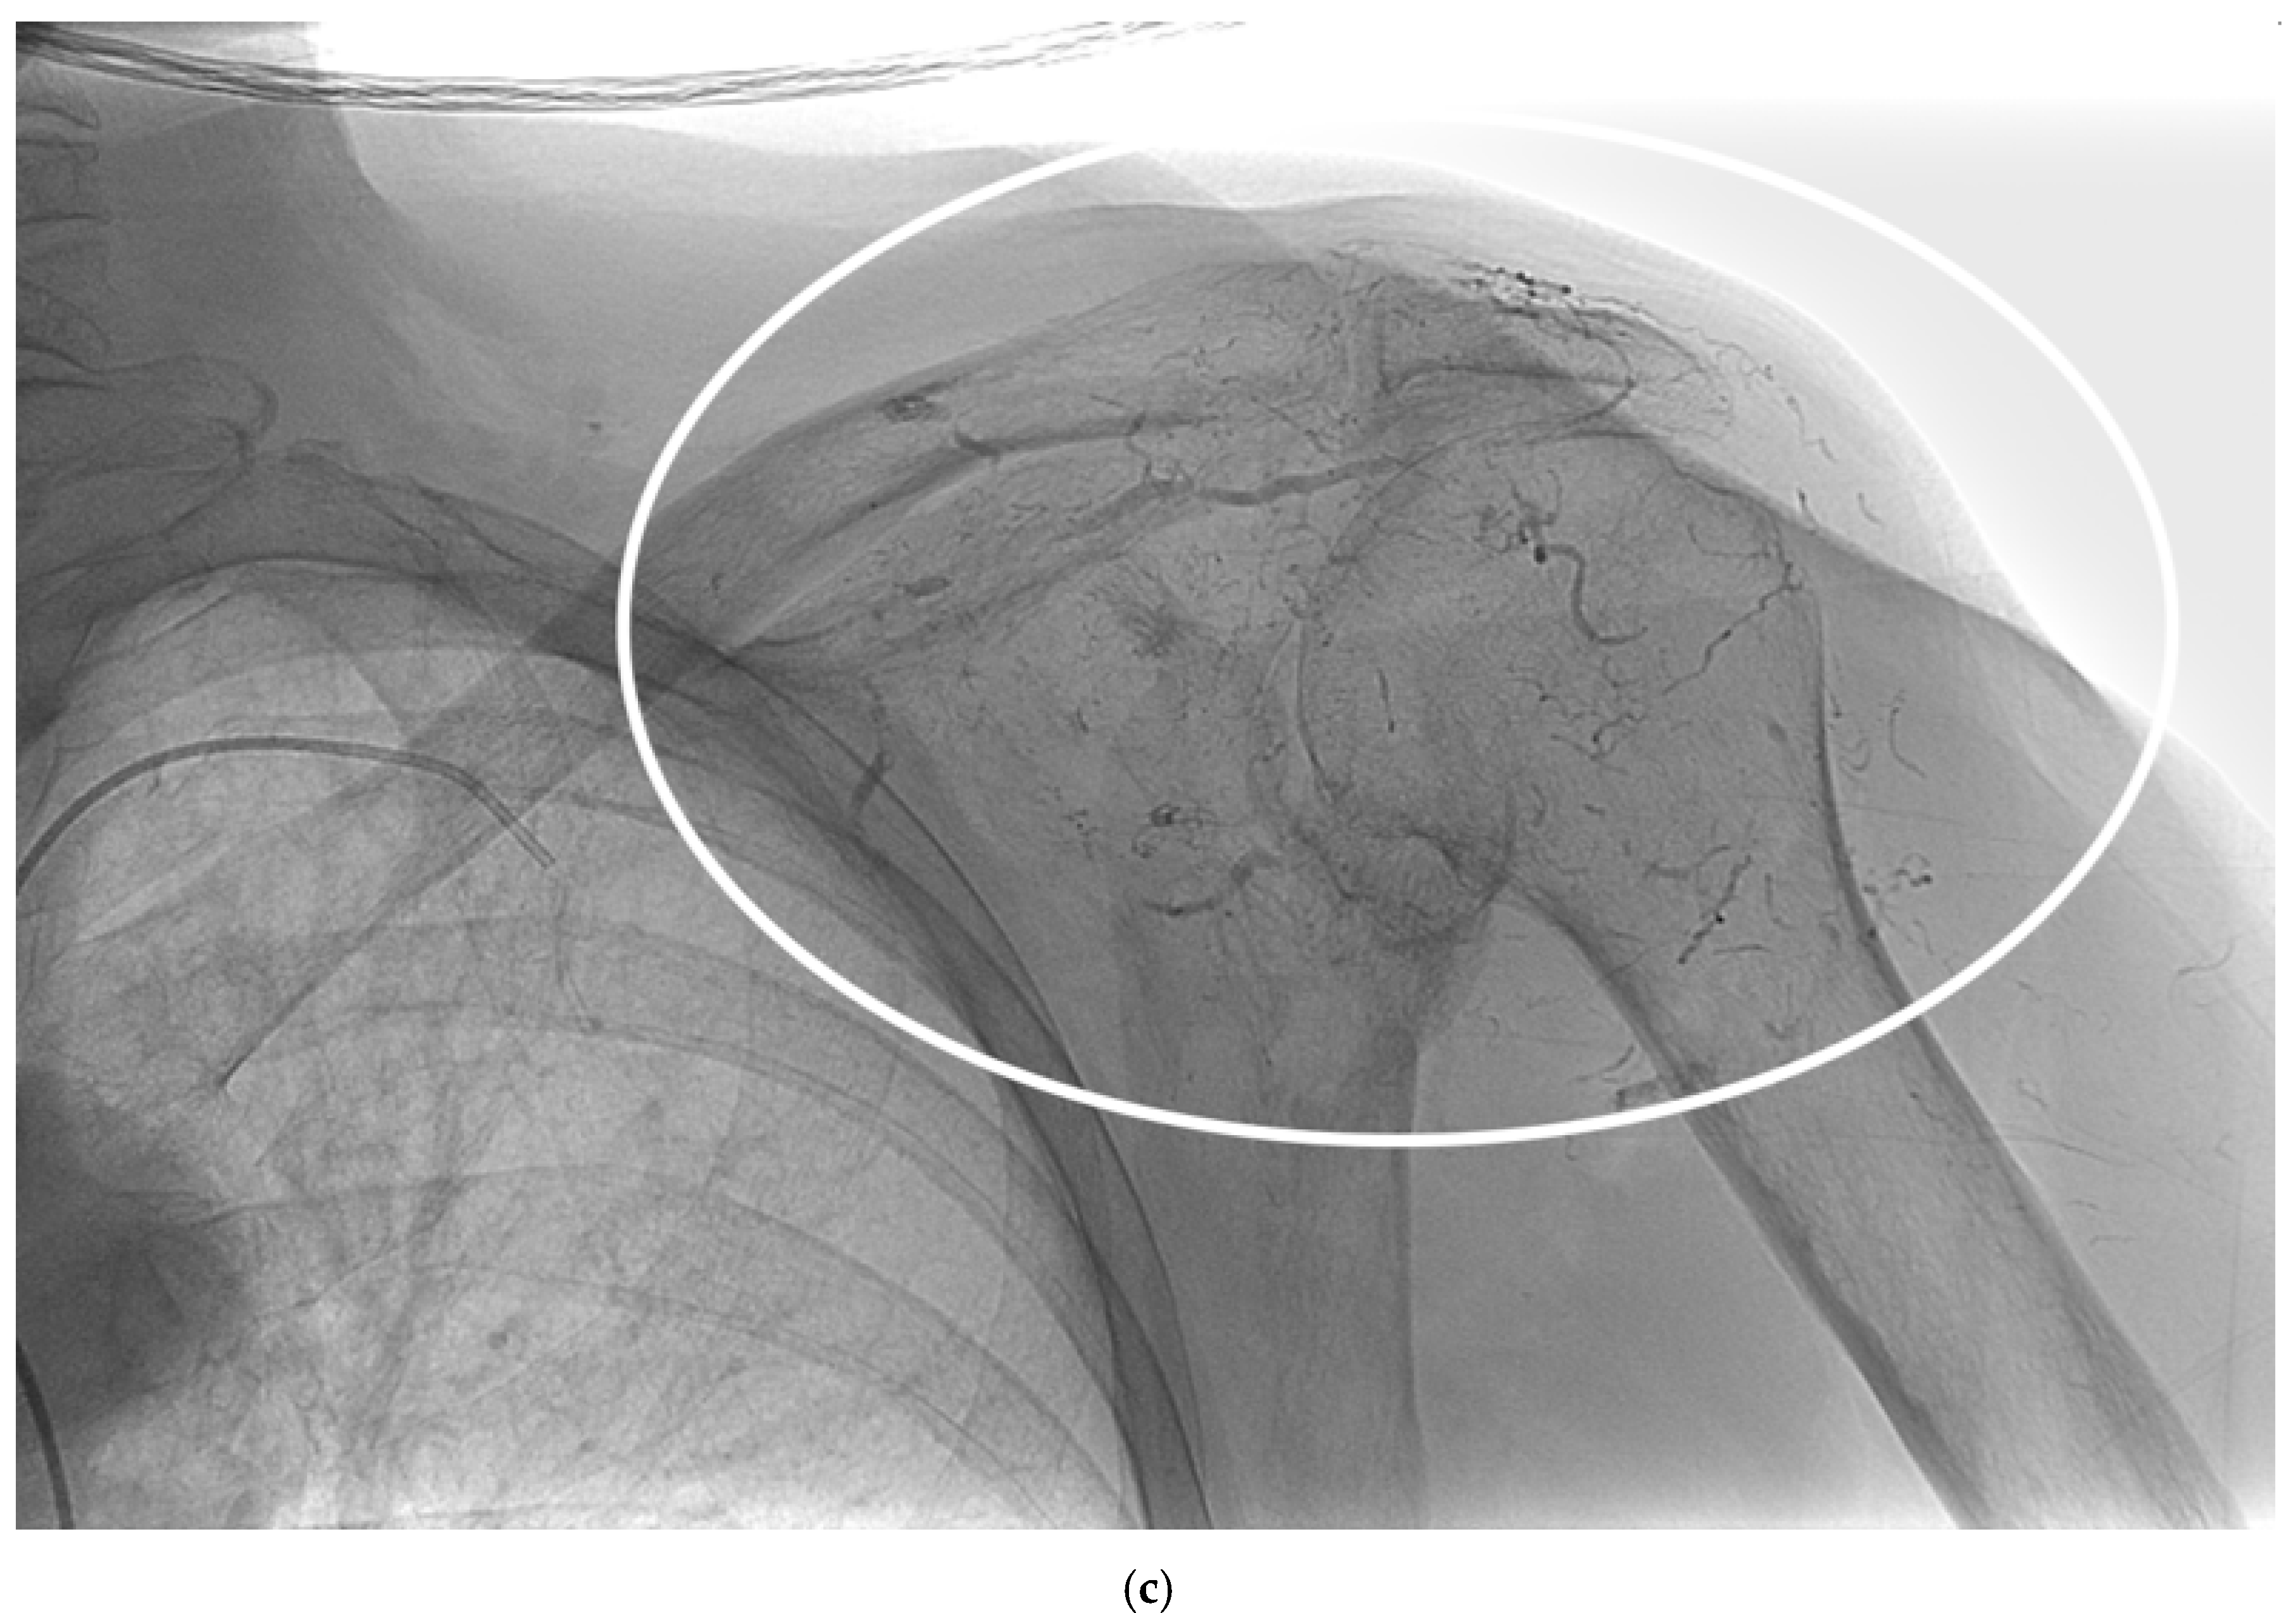

The study cohort included 14 patients (9 males, 5 females) with a mean age of 62 years (SD 10.2) who underwent palliative arterial embolization for scapular metastases. The primary arteries embolized were the circumflex scapular artery, the dorsal scapular artery and the thoracic-acromial trunk. A mixture of Glubran and Lipiodol in a 1:2 ratio was used for embolization, with an average of 1.1 mL (Range 0.5-1.5 mL) used per procedure (Figure 2).

Figure 2. A 62-year-old man with a single metastasis from lung cancer in the body of the scapula; a) arteriography performed with a 5F vertebral catheter positioned in the subclavian artery shows pathologic vascularization of the tumor and b) post-embolization arteriography performed from the same injection point, demonstrating near complete devascularization of the scapular lesion. C) Non-subtracted digital fluoroscopy demonstrating extensive presence of lipiodol/Glubran mixture in the embolized vessels (circle).